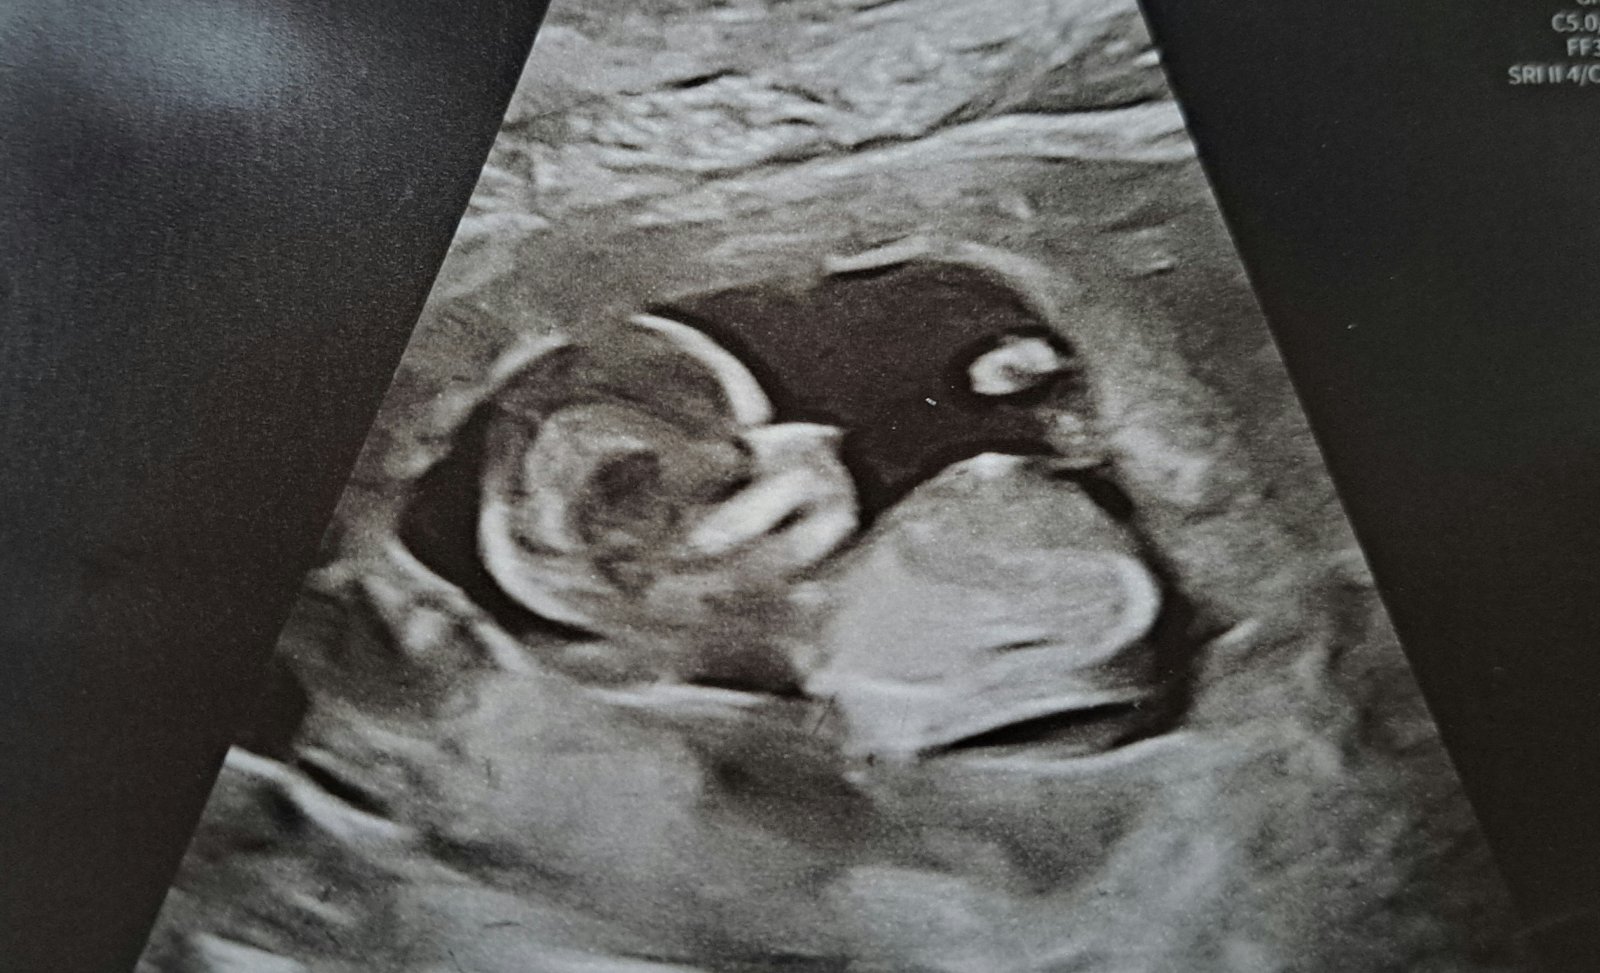

Naše krásná bublinka 🥰💞❤️🍀🍀🍀🍀